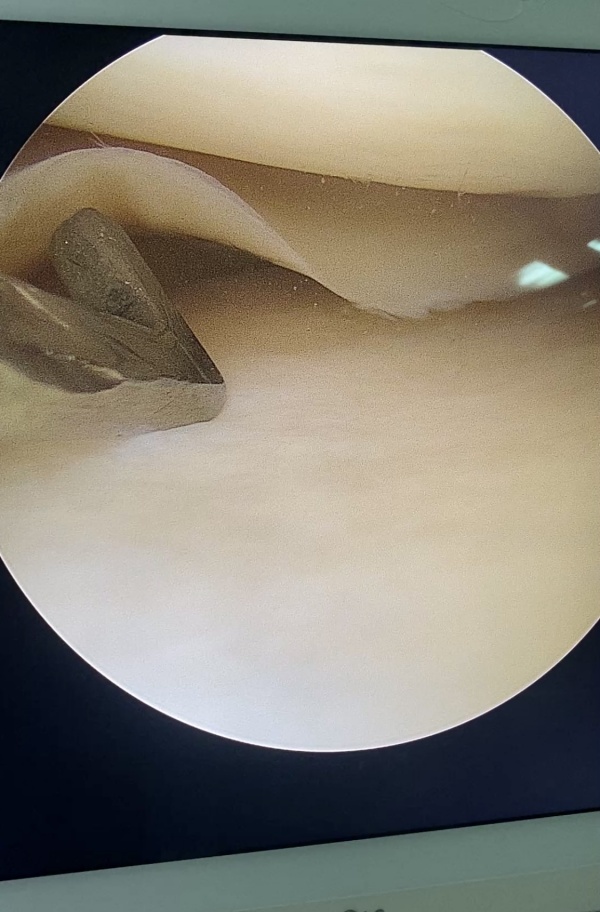

ARTROSCOPIA:

La Cirugía Artroscopica es el mayor avance técnico en el campo de la patología del aparato locomotor de las últimas décadas. Hoy en día tenemos la posibilidad de abordar la práctica totalidad de articulaciones grandes y medianas simplemente con 2 ó 3 orificios de 3 milímetros. A través de pequeñas incisiones introduciremos una cámara artroscópica que nos permite ver el interior de la articulación a gran aumento y también el instrumental preciso para la cirugía. El ingreso hospitalario suele ser menor a 24 horas y la recuperación menor de 6 semanas.

- Rodilla: roturas meniscales, rotura de ligamentos cruzados, malalineaciones de rótula, defectos cartílago.

Artroscopia de rodilla

Menisco

Espacio articular